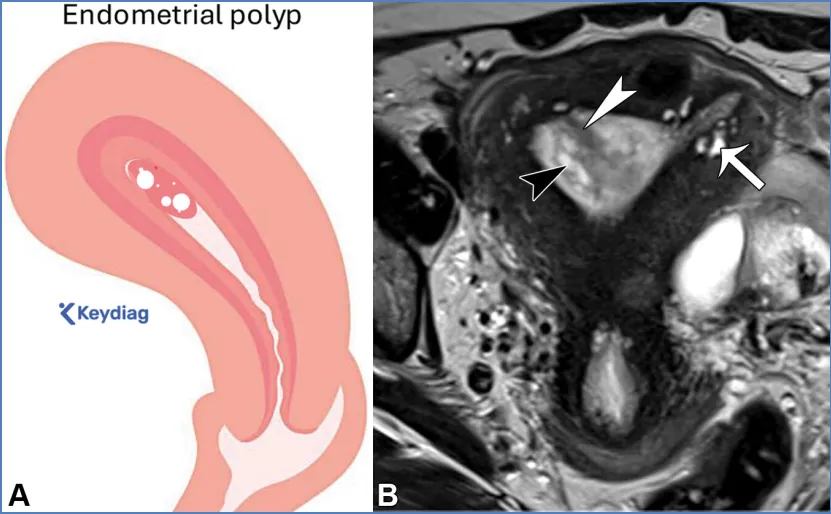

卵巢——卵巢是可活动的腹膜内器官,由卵巢韧带(连接卵巢与子宫角)、卵巢系膜(将卵巢固定于阔韧带)和悬韧带(连接卵巢与盆腔侧壁并包裹性腺血管)支撑(图6)(36)。性腺动脉起源于肾动脉下方的腹主动脉;右侧性腺静脉汇入下腔静脉,左侧性腺静脉汇入左肾静脉。性腺静脉直径大于0.8厘米为异常,尽管性腺静脉直径与静脉反流之间的相关性较差(37)。性腺血管走行于腰大肌前方、输尿管外侧。 卵巢的表现随月经周期阶段和绝经状态而变化。绝经前卵巢为较大的椭圆形结构,在T2加权成像上能清晰显示分区解剖结构,包括T2低信号的皮质、T2等信号的髓质(含疏松排列的基质和血管)、T2高信号的薄壁卵泡,偶尔可见黄体(19,38)。黄体因有黄素化的卵泡膜细胞而呈现T2等信号的厚壁,在退化过程中会变得锯齿状。非出血性黄体中央呈T1低信号、T2高信号,而出血性黄体中央呈T1和T2高信号,有时可见血细胞比容平面。静脉注射对比剂后,卵巢皮质和基质轻度强化,强化程度低于子宫肌层,而黄体壁则表现为早期明显强化(38)。绝经后卵巢比绝经前卵巢小,皮质和髓质呈T2等信号至低信号,偶尔可见小囊肿(38)。表S2以及图7-10详细描述了常见的生理性和其他良性卵巢表现的MRI特征(19,38-42)。图7. 两位不同患者的正常经前卵巢,突出显示了生理学观察结果。(A)示意图显示了带有卵泡的经前卵巢。(B)一位27岁女性患者的轴位T2加权图像显示一个椭圆形卵巢,具有T2低信号皮质(箭头)、T2等信号髓质(白色*)和多个T2高信号卵泡(黑色*)。(C、D)一位30岁女性患者的轴位T2加权(C)和对比增强脂肪抑制T1加权(D)图像显示了黄体(CL),这是经前女性常见的生理学表现。其影像学表现随发育阶段而变化。典型的黄体在T2加权成像上表现为囊性结构,中心呈高信号,壁厚且呈锯齿状,信号强度中等(C中的箭头),在静脉注射造影剂后明显强化(D中的箭头)。图8. 一名34岁闭经女性患者的多囊卵巢综合征与继发性非典型子宫内膜增生。(A)示意图展示了多囊卵巢,这是一种常见的内分泌疾病,影响高达10%的育龄女性。多囊卵巢综合征的诊断依据Rotterdam标准,该标准要求满足以下三项中的至少两项:多囊卵巢、月经稀发或无排卵,以及高雄激素血症。多囊卵巢的定义为:至少一侧卵巢的体积达到10毫升或以上,或者每个卵巢有20个或更多的卵泡(详见表S2)。(B)轴位T2加权图像显示双侧多囊卵巢增大,中央为T2等信号基质(小*),周围有多个T2高信号卵泡。(C)矢状位T2加权图像显示子宫内膜腔内呈不均匀的T2等信号(大*),对应活检证实的非典型子宫内膜增生。在所有增强后序列(包括延迟图像,未显示)中,非典型子宫内膜增生的强化程度低于子宫肌层,这与子宫内膜癌的强化模式相似。图9. 一名27岁女性患者的右侧卵巢扭转,该患者表现为急性盆腔疼痛。轴位T2加权图像显示右侧卵巢(RO)增大且水肿,伴有外周卵泡(箭头所示)。与正常的左侧卵巢(*)相比,右侧卵巢位置异常,位于子宫(U)的中央后方。卵巢扭转的其他表现(未显示)可能包括血管蒂扭转以及强化程度不一,这取决于缺血程度或是否存在梗死。图10. 一位43岁女性患者的输卵管卵巢脓肿,该患者在子宫内膜活检后出现恶心、呕吐和盆腔疼痛症状。轴位T2加权像(A)和对比增强脂肪抑制T1加权像(B)显示左侧附件区有一个多房囊性肿块。该肿块内含有脓性液体,在T2加权像上表现为不同的信号强度(A中的*),并具有增厚的强化壁以及多个强化分隔(B中的箭头)。高b值扩散加权像和ADC图(未显示)显示扩散受限,与脓液的存在相符。经皮引流后获得的细菌培养结果显示大肠杆菌阳性。——输卵管从子宫角延伸至卵巢(39)。近端的壁内部分穿过子宫肌层;远端带有伞端的漏斗部开口于卵巢附近的腹膜腔。输卵管被阔韧带的输卵管系膜包绕(图6)。在MRI上,它们表现为卵巢和子宫之间的T2低信号管状结构。子宫体和宫颈解剖。——子宫由子宫体和宫颈组成,宫颈下段(或子宫颈外口部)突入阴道上部(图2、3)(24、25、43)。在T2加权成像上,绝经前子宫的子宫体(子宫内膜、结合带和外肌层)和宫颈(宫颈管、宫颈内间质和宫颈外间质)均显示出清晰的分区解剖结构。绝经后或接受放射治疗后,这种分区解剖结构会变得不清晰(24、25、43)。子宫内膜腔由均匀的T2高信号子宫内膜衬里,延伸至同样为T2高信号的宫颈管(38)。子宫内膜厚度在子宫矢状面中部沿子宫长轴测量,其数值会随绝经状态和月经周期阶段而变化(表S3)(38、44-49)。对于有绝经后出血的患者,子宫内膜厚度≥5mm为异常;而无症状患者的阈值则不太明确(50)。结合带(子宫内肌层)呈T2低信号,向尾侧延续为T2低信号的宫颈内纤维间质。子宫外肌层呈T2等信号,过渡为宫颈外间质的T2等信号。正常结合带厚度≤8mm,若无微囊肿则可达11mm(45)。 子宫峡部是子宫体与宫颈之间的过渡区,在矢状位T2加权成像上表现为局限性缩窄,在轴位斜向T2加权成像上可见子宫血管进入(图2、3)(24、25)。宫颈内口和外口分别是宫颈管的上下开口。宫颈围绕宫颈管,包括上皮衬里和宫颈间质(43)。宫颈上段由腺状柱状上皮覆盖,宫颈下段(包括子宫颈外口部)由鳞状上皮覆盖。鳞状上皮与柱状上皮的交界处(鳞柱交界)在生育年龄具有动态变化,是大多数宫颈癌前病变和宫颈癌的起源部位。宫旁组织由主韧带和宫骶韧带构成,从宫颈两侧延伸至盆侧壁,包绕子宫血管、神经和输尿管(图2、3)。表S3以及图11-13概述了常见的子宫体和宫颈良性病变的MRI特征(38、44-49)。图11. 一位50岁女性患者的子宫内膜息肉,该患者在乳腺癌切除术后接受他莫昔芬治疗。(A)子宫矢状面示意图显示息肉状子宫内膜病变,伴有因子宫内膜腺体扩张而形成的囊性病灶。(B)冠状斜位T2加权像显示子宫内膜内有一个带蒂病变,具有T2低信号的纤维血管核心(白色箭头)和T2高信号病灶(黑色箭头),这些表现提示为子宫内膜息肉。通常可见明显的强化,与子宫肌层的强化程度相似(未显示)。明确诊断需要宫腔镜下切除,因为子宫内膜息肉、增生和肿瘤可能同时存在,且在影像学特征上可能重叠。偶然可见子宫腺肌症,表现为结合带内存在微囊肿(箭头所示)。图12. 弥漫性和局灶性子宫腺肌病(或子宫腺肌瘤)。(A)子宫矢状面中部的插图显示了弥漫性子宫腺肌病(上图)与局灶性子宫腺肌病或子宫腺肌瘤(下图)的对比。(B、C)两名不同的月经过多患者的矢状位T2加权图像显示,T2低信号的交界区(JZ)弥漫性增厚,伴有散在的T2高信号微囊肿(B中的实线),以及前部交界区伴有微囊肿的局灶性肿块样不对称增厚(C中的虚线)。这些表现是由于子宫肌层内存在异位子宫内膜腺体和间质(微囊肿)以及反应性平滑肌增生(交界区增厚)所致。图13. 纳博特囊肿与隧道簇。插图(A)及两名不同患者的子宫正中矢状面T2加权图像(B、C)显示,浅层宫颈基质内的单房囊肿为典型的纳博特囊肿(A图左图;B图),而向宫颈基质深部延伸的多房囊肿为隧道簇的特征性表现(A图右图;C图)。务必在增强图像上排除强化实性组织的存在(未显示),因为多房性宫颈病变中若出现强化实性组织,应怀疑宫颈胃型腺癌。可能需要进行宫颈锥形活检以明确诊断。子宫在骨盆内的位置会因膀胱充盈程度和盆腔瘢痕情况而有所不同。倾位指的是宫颈与阴道之间的角度:前倾位是向前倾斜,后倾位是向后倾斜(图14)(38)。屈曲描述的是子宫体与宫颈之间的角度:前屈是向前弯曲,后屈是向后弯曲(38)。图14. 插图(A)和磁共振图像(B、C)显示了女性骨盆内子宫的各种位置。子宫倾(Version)指的是宫颈与阴道之间的角度:A中的上组插图将该角度显示为黄线相对于红线的倾斜度。前倾(Anteversion)指向前倾斜,后倾(Retroversion)指向后倾斜。子宫屈(Flexion)描述的是子宫体与宫颈之间的角度:A中的下组插图将该角度显示为蓝线相对于黄线的倾斜度。前屈(Anteflexion)指向前弯曲,后屈(Retroflexion)指向后弯曲。两名患者的矢状位T2加权图像(B、C)中,B显示的是前倾前屈位子宫,C显示的是后倾后屈位子宫。阴道是一个纤维肌性结构,通过膀胱阴道隔与膀胱相隔,通过直肠阴道隔与直肠相隔(图4)(51)。在轴位T2加权成像上,绝经前阴道通常呈H形或W形塌陷,具有高信号的黏膜皱襞和低信号的壁。绝经后,皱襞消失,阴道壁厚度变薄。阴道上部有由突出的宫颈形成的穹窿,阴道下部通过阴道口开口于外阴前庭。表S4和图15详细描述了常见良性阴道病变的MRI特征(51-53)。图15. 四个不同患者的矢状面示意图(A)和轴位T2加权图像(B–E)显示了阴道囊肿、斯基恩氏腺囊肿以及尿道憩室。巴氏腺囊肿:位于耻骨联合处或其下方阴道后外侧壁的单房囊肿(A中的灰色椭圆形,B中的T2高信号囊性病变)。加特纳管囊肿:位于耻骨联合处或其上方阴道前外侧壁的单房囊肿(A中的蓝色椭圆形,C中的T2高信号囊性病变)。斯基恩氏腺囊肿:位于耻骨联合下方、阴道前方、尿道下段外侧的单侧或双侧小单房囊肿(A中的浅黄色椭圆形,D中的T2高信号囊性病变)。尿道憩室:在耻骨联合附近,尿道中远端后外侧出现的圆形、椭圆形或U形T2高信号液性囊袋状突起(A中的尿道囊袋状突起)。在罕见情况下,尿道憩室可能完全环绕尿道(E中的T2高信号环形囊性病变)。外阴由女性外生殖器组成(图16)(53)。阴阜位于耻骨联合前方,由脂肪组织构成。大阴唇是位于阴阜下方并与其相连的厚皮肤皱襞。小阴唇是大阴唇之间较薄的皱襞,向前会合于阴蒂头。小阴唇之间的前庭包含尿道外口(尿道口)和阴道口(阴道开口)。图16. 示意图(A)和轴位T2加权图像(B)显示了外阴区域或女性外生殖器。阴阜位于耻骨联合前方,由脂肪组织构成。大阴唇是位于阴阜下方且与其相连的厚皮肤皱襞。小阴唇是大阴唇之间较薄的皱襞,向前汇聚于阴蒂头。小阴唇之间的前庭前部有尿道外口(尿道口),后部有阴道口(阴道开口)。参考文献:https://doi.org/10.1148/rg.250029